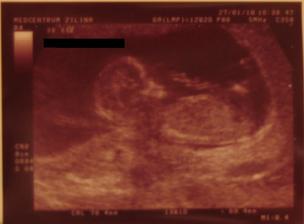

Onedlho nás uvidíte ako malé bodky na sone,

Či budeme dve, či jedno, to je v rukách vyššej moci,